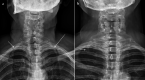

Fig. 1

TOS. Standard chest X-ray. Patient with bilateral cervical ribs: a right (short arrow) and left (long arrow) cervical rib. Patient with unilateral cervical rib: b right cervical rib (arrow)